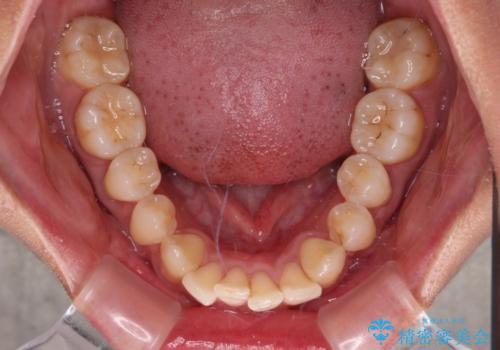

- 上顎前歯の突出感を気にして来院された患者様です。

舌の突出癖の影響で、歯列が前方に飛び出いた形態となっている状態でした。

抜歯矯正とするような歯列ではないため、舌のトレーニングを行いながら歯列を側方に拡大させることで口元の突出感を改善することとしました。